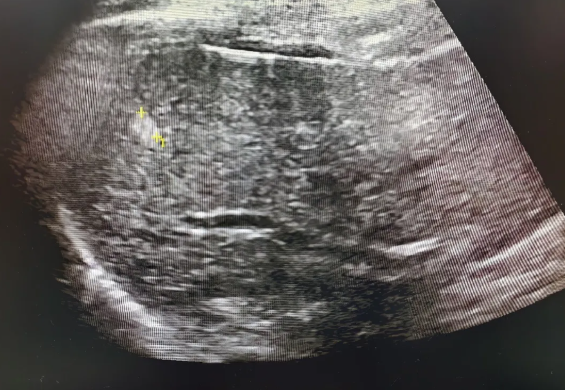

腹部超声检查是发现及诊断肝血管瘤的首选影像学方法,具有很高的灵敏度和特异性。

必要时(如有乙肝病史、肝硬化病史的情况下出现不典型影像)可以结合CT、核磁或者造影等检查综合判断。